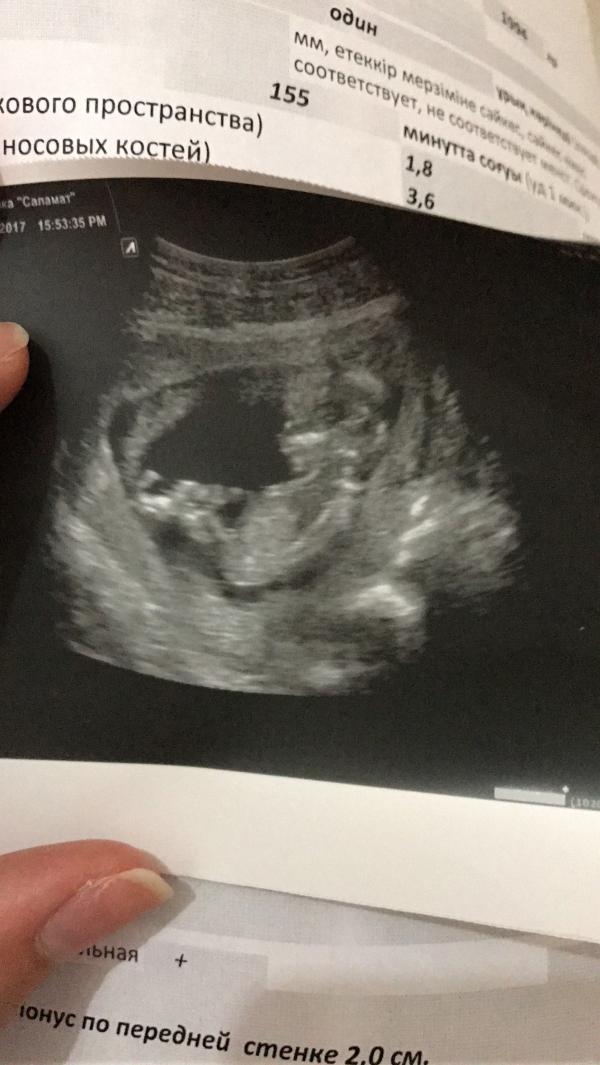

Узи на 13ой недельке😇😇😇 как думаете,кто будет?) мальчик или девочка?🙈